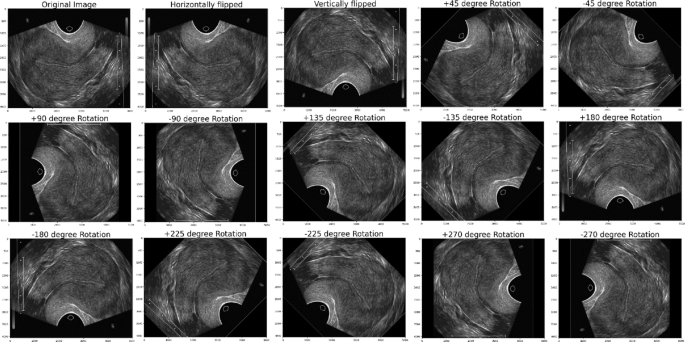

The proposed FCAU-Net model was designed to classify the PCOS infected and Normal healthy images. The FCAU-Net research methodology is shown in Fig. 2. The overall research methodology of FCAU-Net initiates with stage 1 that performs collection of 3800 PCOS ultrasound Images Dataset from KAGGLE having 1900 PCOS infected images and 1900 Normal healthy images47. Stage 2 deals with dataset preprocessing that segregates the images based on normal and PCOS symptoms. Then the Labelling of the image is done followed by data augmentation by generating 14 augmented images for each image in the dataset resulting with 53,200 images. The data augmentation was performed using horizontal flipping, vertical flipping, rotation with positive and negative angle of 45, 90, 135, 180, 225, 270 degrees. The data augmented cropped images are subjected to generate fuzzy contrast enhanced image vector. Stage 3 fits the HEG images are fitted with the existing CNN models like DenseNet, AlexNet, VGG19, ResNet, Inception, UNet and Attention UNet to select the best CNN model. The Attention U-Net found to detect the existence of PCOS with accuracy above 80%.

The labelled PCOS ultrasound images subjected to image cropping by finding the biggest contour and extract the extreme points to form the crop images. The image cropping was performed in order to focus on the significant image features. The cropped images are performed with data augmentation that 14 images for each image in the dataset resulting with 53,200 images. All the data augmented images are subjected to enhance the brightness of the image by forming Histogram equalized image, CLAHE image and Fuzzy Contrast Enhanced image. This work forms both Histogram equalized image and CLAHE with the intent of performance evaluation as both of them serves a distinct purpose. The normal Histogram equalization of the image works for the entire image by stretching the pixel intensity. Though CLAHE is a method of histogram equalization, it applies histogram for small adaptive regions that prevents noise in homogenous areas. The FCE images, known for their high brightness, are validated using the PSNR ratio and processed through the Fuzzy Contrast Enhanced module. The FCAU-Net framework, depicted in Fig. 5, uses these FCE images as input. The images are passed through four encoder blocks and four decoder blocks. The encoder-decoder feature maps are combined using the Feature Fusion Context (FFC) module, which extracts positional and contextual characteristics to generate optimized fused feature maps.

After labeling, the image cropping was done to form the cropped image. The results of the PCOS Ultrasound images before and after Image cropping are shown in Fig. 10. The cropped PCOS Ultrasound images are subjected to data augmentation to form 14 images for each image resulting with 53,200 images data augmented cropped images. The results obtained from the data augmented PCOS infected and normal healthy ultrasound images are shown in Figs. 11 and 12 respectively.